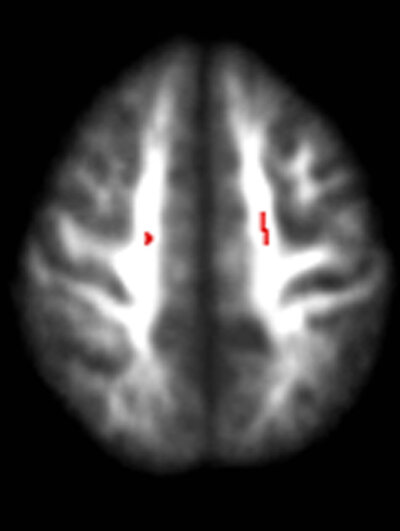

The team found damaged nerve tissue in the brains of the teens who drank. The researchers believe this damage negatively affects attention span in boys, and girls' ability to comprehend and interpret visual information.

Damage to the brain of a teenage drinker, top view